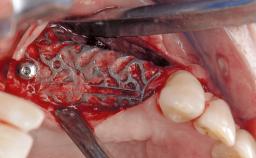

Surgical Treatment of Peri-Implantitis in the Posterior Mandible Associated with Hard- and Soft-Tissue Reconstruction

Paolo Casentini demonstrates that peri-implantitis can be successfully treated even at an advanced stage. He discusses a case in which the existing implants and prostheses were both retained while regenerating the defect and creating a band of keratinized tissue. A 69-year-old female patient was referred by her general dentist for evaluation of a recurrent infection at previously placed and restored implants in the posterior left mandible. The patient’s chief complaint was recurrent swelling and pain in the molar region of the left posterior mandible with discomfort during brushing in the same area. The patient reported receiving two implants (36 and 37) nine years earlier.